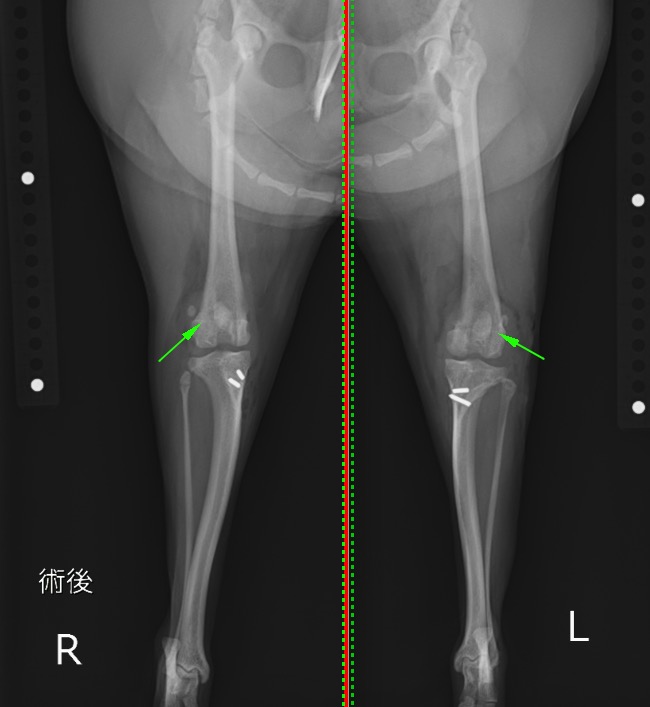

術後のX線写真を見ていただくと。緑矢印で示した膝蓋骨が滑車溝内(大腿骨の中央)に整復されているのが分かります。

術後のX線 膝蓋骨の位置が正しい位置に整復されている